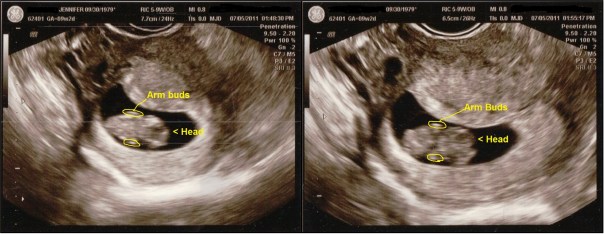

Early Ultrasound 9 weeks 2 days

Yesterday I had another early ultrasound. This was the follow-up to the one I had two weeks ago. The baby was very small at the time so they wanted to make sure a twin wasn’t hiding in there.

Apparently there wasn’t. There’s just one sweet little baby in there. She had no trouble finding the baby this time. We saw the heartbeat and it was 167. We also got to see the little one give us a few wiggles and shimmies 🙂

(Click on photos to enlarge them.)

The head is to the right and you can see the baby’s arm buds!